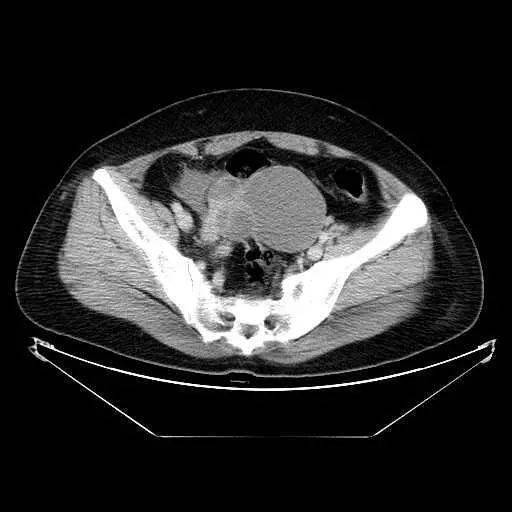

【读片】盆腔肿块—ct平扫,请大家看看!

今天给大家分享的第一病例7岁女孩,以右下腹痛来诊,在ct平扫检查中

盆腔占位/ct/公布结果/100128